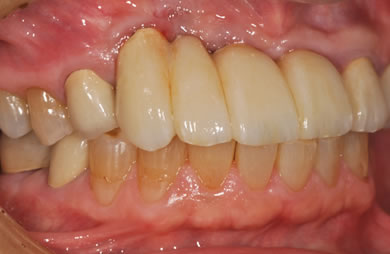

治療後

• 治療後